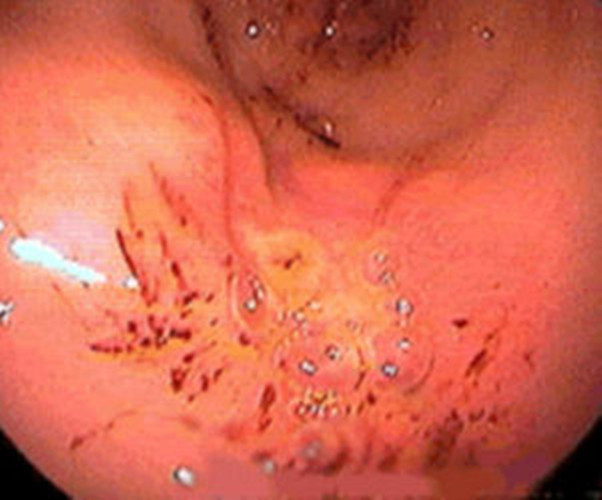

淺表型糜爛出血慢性胃炎

淺表型糜爛慢性胃炎